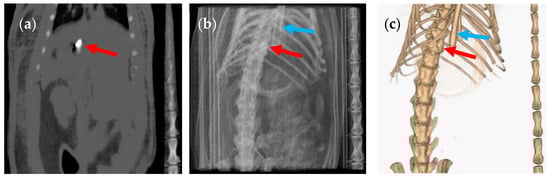

3. Results and Discussion